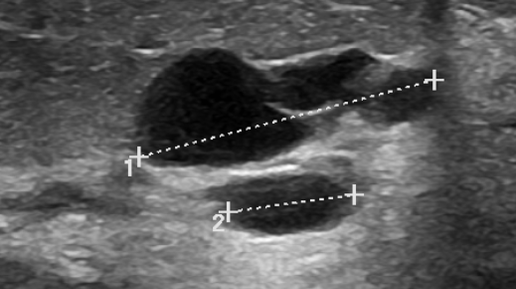

Киста молочной железы – наиболее часто выявляемое изменение её структуры. Образуются кисты из-за скопления увлажняющей проток жидкости в закупоренном выводящем протоке терминальной протоково-дольковой единицы. Скопление жидкости со временем приводит к растяжению протока и увеличению размеров жидкостной полости. При осмотре кисты молочной железы могут проявляться в виде отчетливо пальпируемых, смещаемых образований. Кисты обычно безболезненные, но при их воспалении может появляться не только болезненность в зоне их расположения, но и покраснение и отек кожи, повышение локальной температуры...